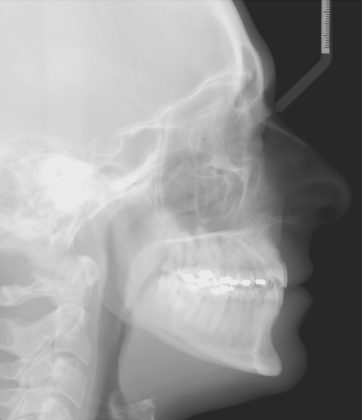

Per formulare corretta diagnosi e piano di cura, lo studio del caso ha previsto la raccolta di documentazione completa standard, ovvero fotografie del viso e intraorali (Figure 1a-e), radiografia panoramica e teleradiografia del cranio in proiezione laterale (Figure 2a-b) per la relativa analisi cefalometrica e modelli di studio.

L’analisi ortodontica e la valutazione parodontale, con particolare riferimento alla posizione della radice del canino superiore destro (1.3), distoinclinata e trasposta alla radice del primo premolare (1.4) come evidente dalla radiografia panoramica e dalle immagini intraorali, ci hanno guidati nella programmazione di un trattamento estrattivo asimmetrico a entrambe le arcate.